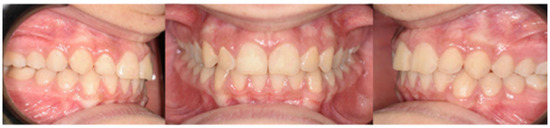

- One year later, class I occlusion was achieved, and the class II elastics were used only during nighttime;

- Two years later, the appliance was deboned, and positioner retainers were given to the patient with the prescription to wear them every night.